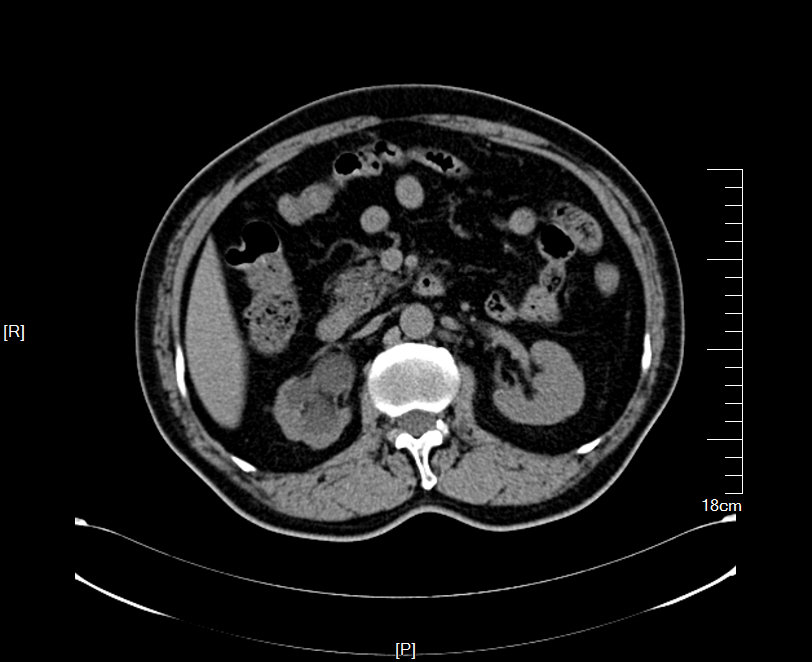

CT检查提示:双侧肾脏重度积水双侧输尿管中段结石 双侧输尿管上段积水扩张

2016年02月手术患者,男性,47岁,河北人,农民,主诉双侧腰部酸胀一年余,伴尿少三天;五年前曾因输尿管结石在当地予以震波碎石3次,后疼痛缓解后未重视,五年来未予以复查,三天前出现尿少,腰部酸胀加重与当地医院就诊后发现病情危重遂来我院求诊,CT:双侧肾脏重度积水,皮质菲薄,双侧输尿管上段扩张明显,双侧输尿管中段结石,左侧结石约1.7cm,右侧约2.8cm左右,GFR:左侧11.7ml/min,右侧16.1ml/min。肾功能:Cr 516umol/L;术前诊断:双侧输尿管结石 双肾重度积水 肾功能失代偿;行双侧经皮肾穿刺造瘘术,保护肾功能,十天后Cr下降至236umol/L,方行双侧输尿管镜检,但由于输尿管梗阻时间太长,输尿管迂曲扩张明显,中段输尿管与周围脏器严重黏连,输尿管镜无法顺利上行,遂行双侧输尿管切开取石术+双侧输尿管裁剪成型术。